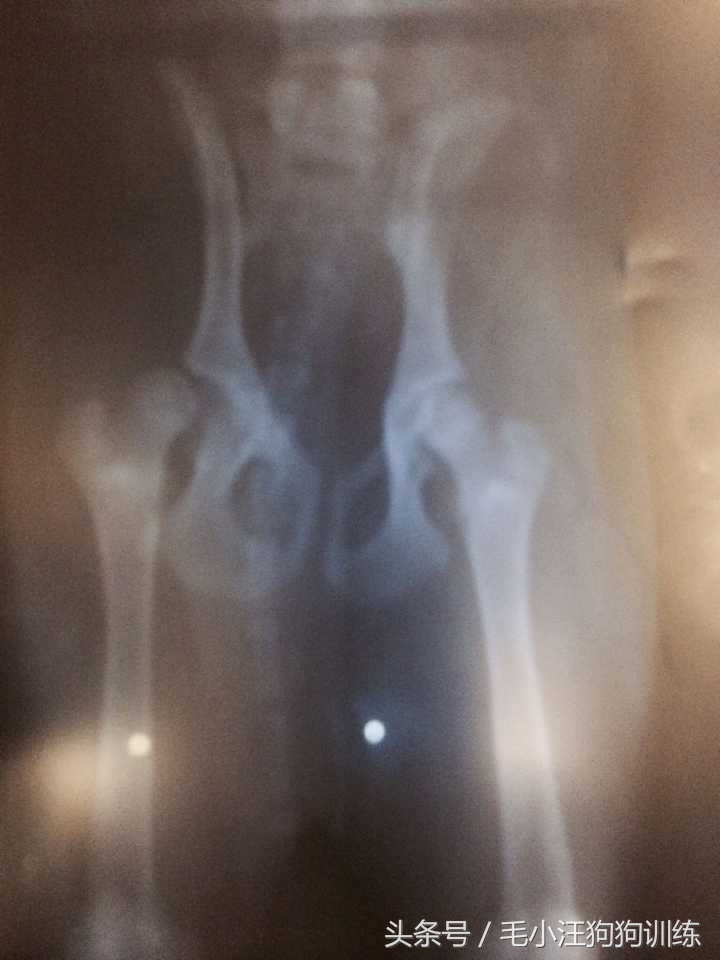

还得从前几个月说起,某一天晚上,睡梦中迷糊的我突然听见pepper的一声惨叫,而后几天就发现pepper走路一瘸一拐的,就赶紧带着她去拍片子,医生说是先天性的疾病——髋关节韧带断裂脱臼! 就算做了手术也会有后遗症...

后来,经朋友介绍兜兜转转终于寻得一家特别好的宠物医院,马上进行了手术,把pepper脱臼的已磨损的骨头剔除掉,这样就算最后瘸了她也不会痛。手术的过程中我心如刀绞。幸好,还好,手术成功了!!!